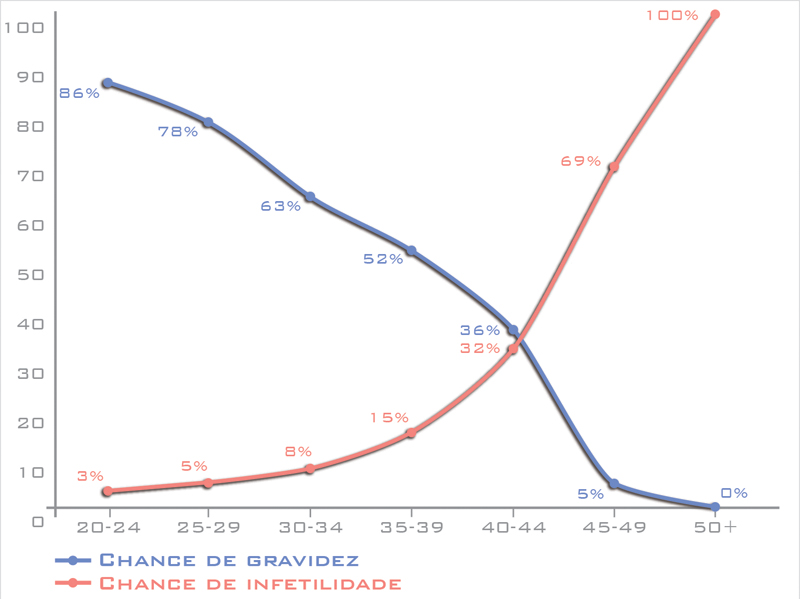

Uma das consequências disso é o aumento do número de casais que precisarão de acompanhamento médico para engravidar, uma vez que a idade da mulher é o fator mais importante para avaliar a fertilidade de um casal. Quando esse desejo é adiado por muito tempo, pode ser necessário o uso de óvulos de outra pessoa no tratamento, uma doadora, para possibilitar a gravidez.

A maior parte dos casais que precisa desta técnica de tratamento é devido à idade da mulher. Um fato que muitas pessoas desconhecem é que as mulheres já nascem com um “estoque” de óvulos determinados que serão usados durante toda sua vida fértil. Não há produção de novos óvulos ao longo da vida.

A maior parte dos casais que precisa desta técnica de tratamento é devido à idade da mulher. Um fato que muitas pessoas desconhecem é que as mulheres já nascem com um “estoque” de óvulos determinados que serão usados durante toda sua vida fértil. Não há produção de novos óvulos ao longo da vida.

Quando se aproximam da menopausa, as mulheres têm uma diminuição importante não só em quantidade, mas principalmente na qualidade desses óvulos do ponto de vista reprodutivo. Isso dificulta uma gestação espontânea e até mesmo em um tratamento complexo como a fertilização in vitro, indicando em alguns casos o tratamento com óvulo de doadora.

Gráfico mostra como a chance de engravidar naturalmente diminui e como a chance de ter diagnóstico de infertilidade aumenta com o aumento da idade da mulher

Outras mulheres que acabam tendo indicação para realizar esse tipo de tratamento são as que apresentam quadro de menopausa precoce (quando acontece antes dos 40 anos) seja qual for o motivo, ou as que apresentem alguma alteração genética e optem por esse tipo de tratamento (existe opção de pesquisa genética de embrião para um grande número de doenças, porisso essa indicação é cada vez mais restrita).